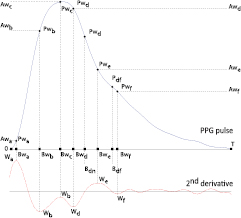

Standard image High-resolution imageAccording to Wang et al (2013), the positions of the a, b, c, d and e waves (here called Wa, Wb, Wc, Wd and We waves and illustrated in figure 6) defined by DDA (Takazawa et al 1998) can provide an insight about the locations of the individual components of the PPG pulse. Additionally, from the inspection of the PPG pulse morphology and the corresponding second derivative, we observed that the negative peak after We (i.e. W f ) can provide information about the location of the second reflection wave and, therefore, it was included in the present work. Based on the waves identified figure 6, the initial parameters and corresponding boundaries of the MG model were determined using a Heuristic approach similar to the one proposed by Wang et al (2013). The initial parameters and boundaries of the proposed model are presented in table 1.

Figure 6. Characteristic waves proposed by Takazawa et al (1998) using DDA and an additional W f wave used in the definition of the initial parameters and boundaries.

Download figure: